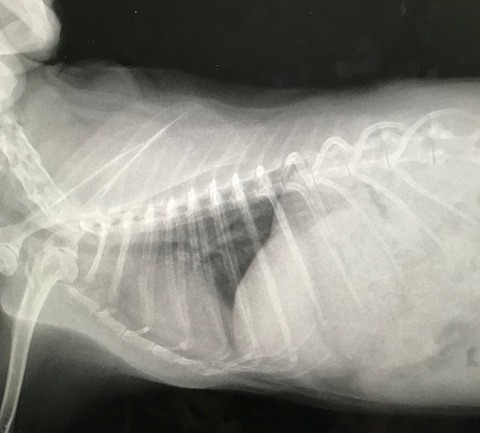

今回は普段の簡易健診にくわえてレントゲンもお願いしました。

ちょっと記憶にあるところで、保護後早々の避妊手術以降、

撮る機会がなかったとちゃうかな、と。

こないだのお腹不調も待合室で食べ始めたから、レントゲンに至らず。

心臓、胸周りほか、腎臓の方とか、一応、何か拾える変化がないか、と…。

所見、特に何って問題は見当たらず、体ん中も準備オーケーでした(。・m・)

レントゲンで見れるよう内臓脂肪もほぼなく健康的